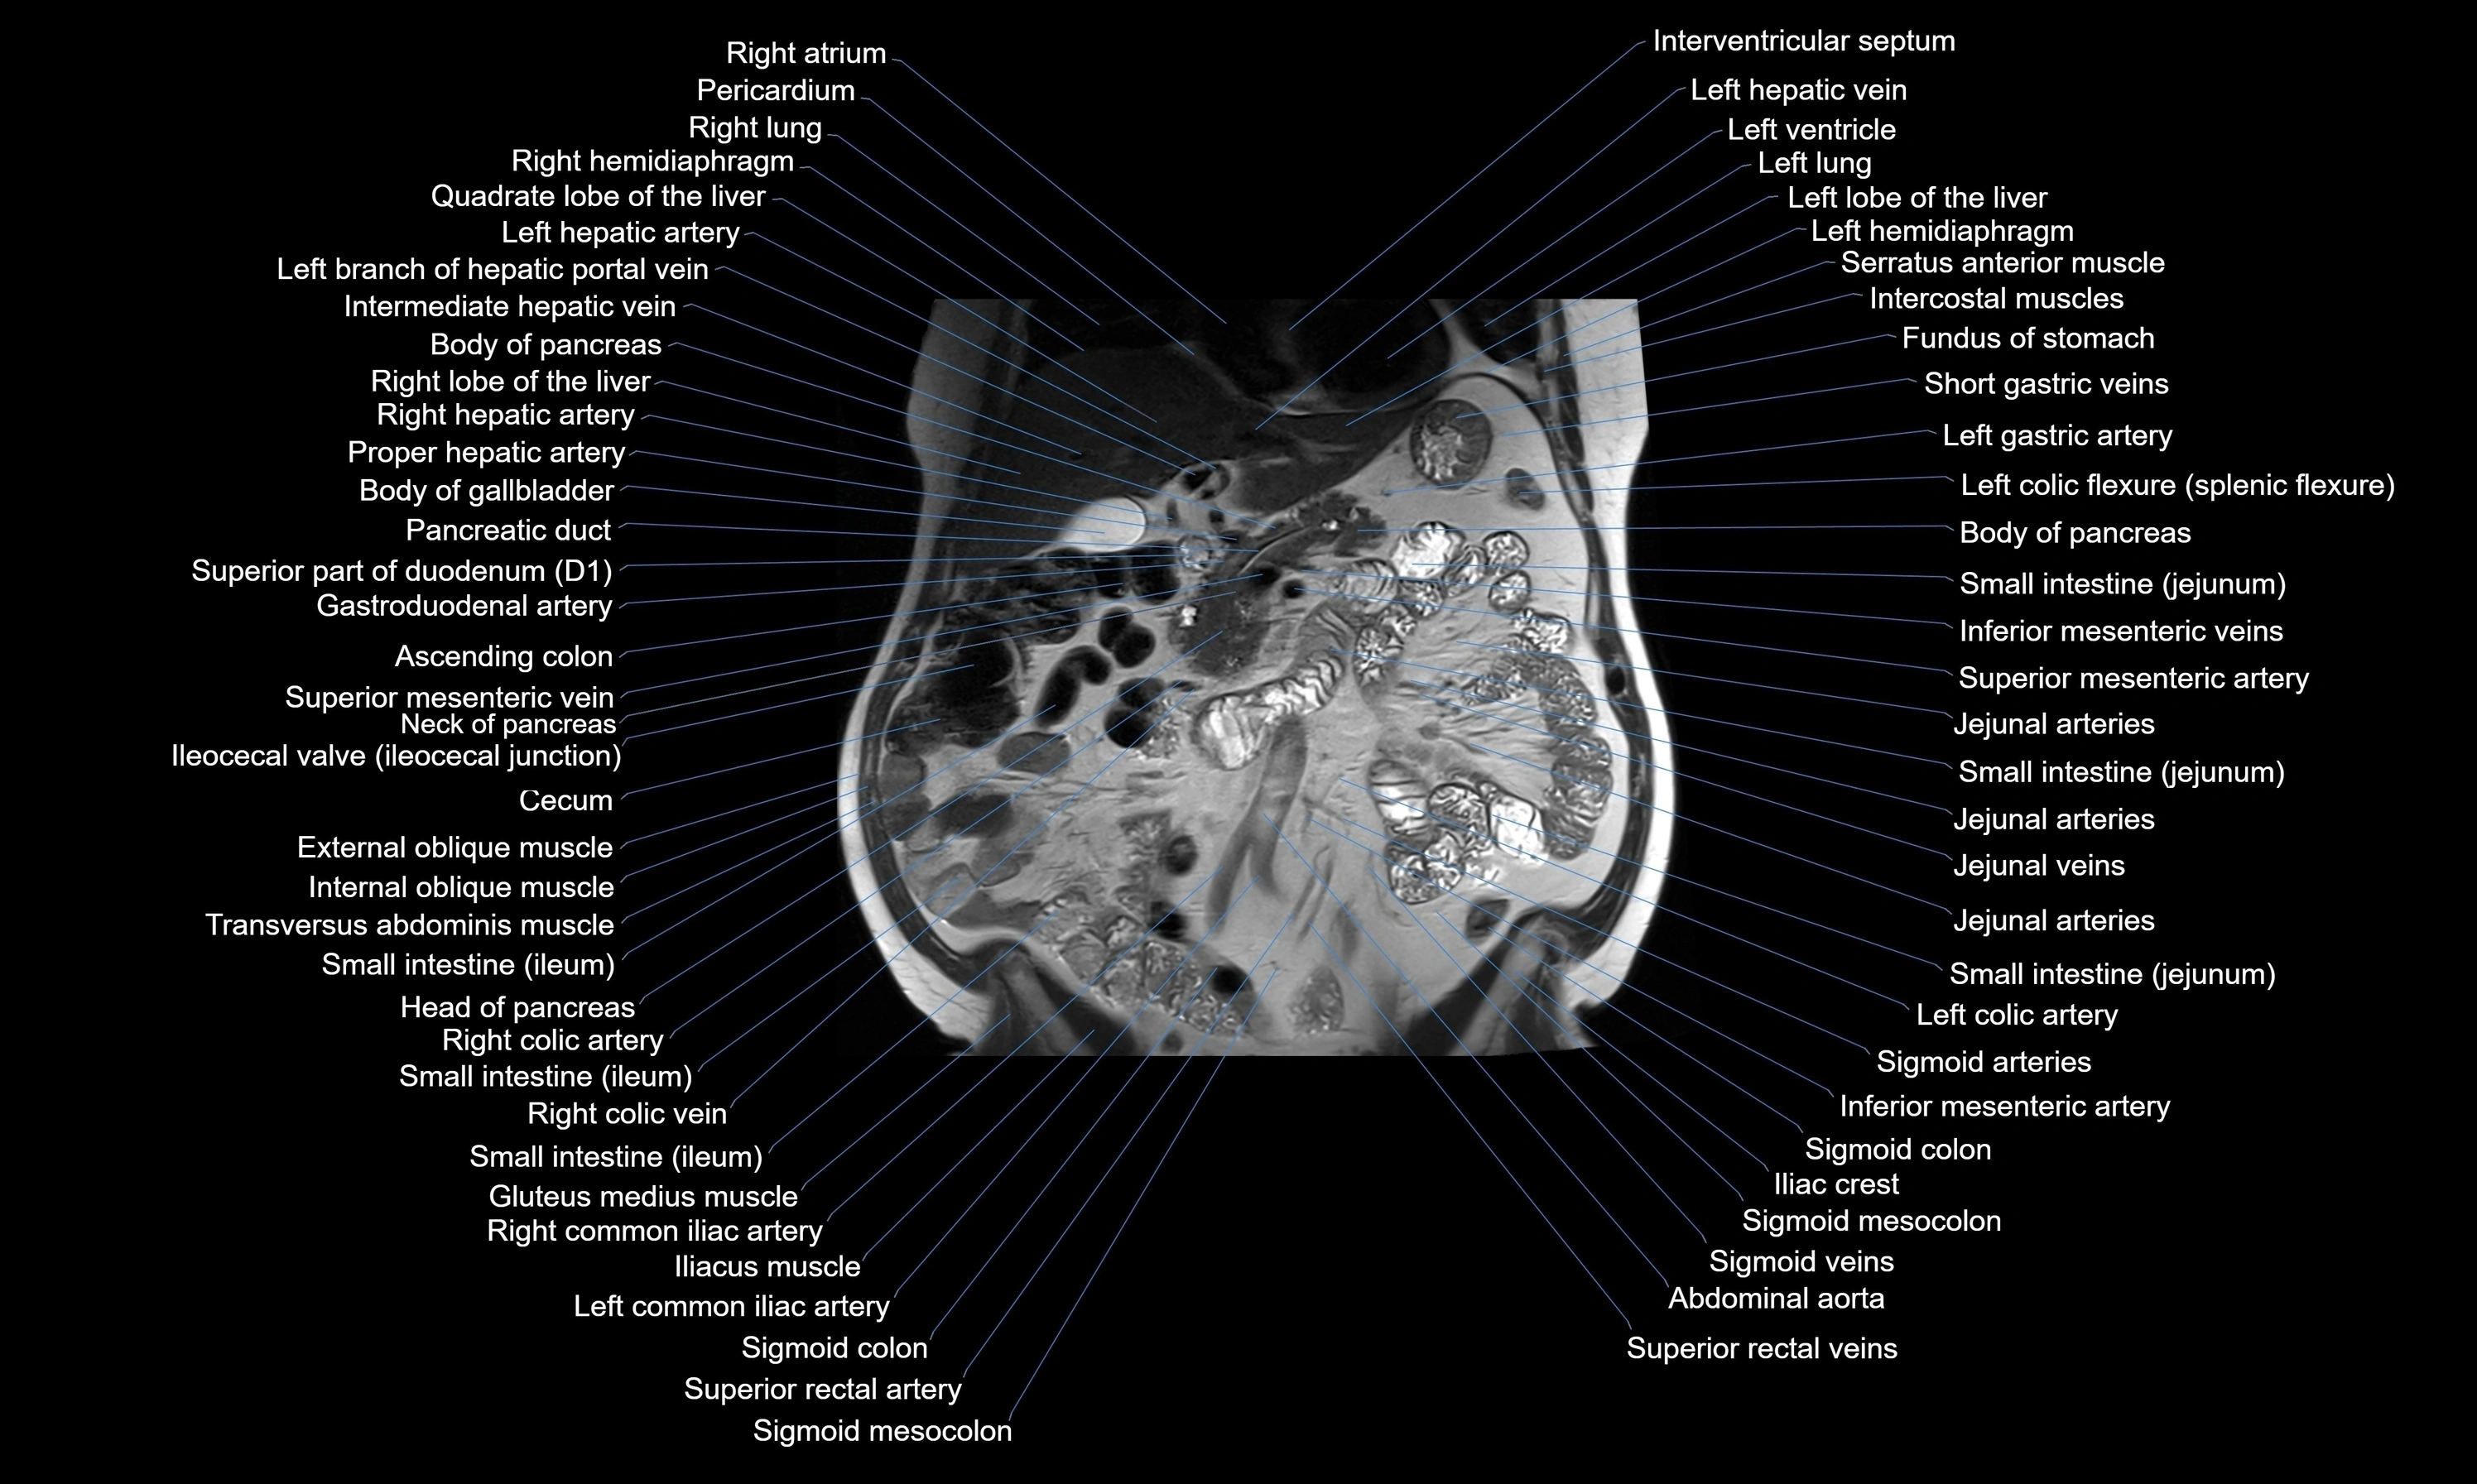

MRI images